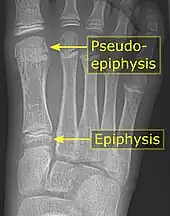

It is common in children to have a pseudo-epiphysis of the first metatarsal.[5] It is common in children to have a pseudo-epiphysis of the first metatarsal.[5]